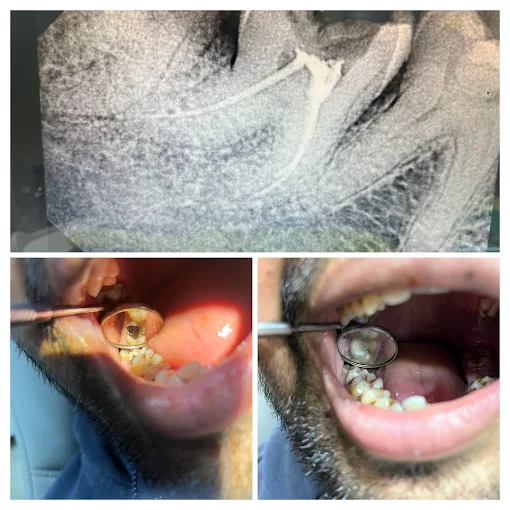

Signs include severe tooth pain, sensitivity to hot or cold, or swelling near the tooth. Our dentist will confirm after an examination.